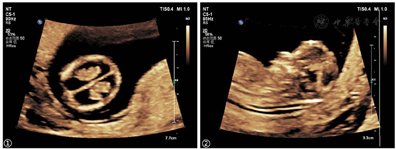

NT超声检查提示:CRL 58 mm,NT 1.4 mm,结构扫查发现双侧侧脑室内脉络丛短小,脉络丛长度/侧脑室长度约0.5,脑干扭曲呈z形,怀疑胎儿脑室扩张及脑干形态异常(图1)。嘱孕妇两周后复查,孕15周超声提示胎儿双侧侧脑室明显扩张,较宽处约11 mm,第三脑室宽约2.3 mm,Z形脑干,小脑横径8.2 mm(小于第1百分位),提示小脑发育不良(图2):双侧侧脑室明显扩张,小脑发育不良,Z形脑干。